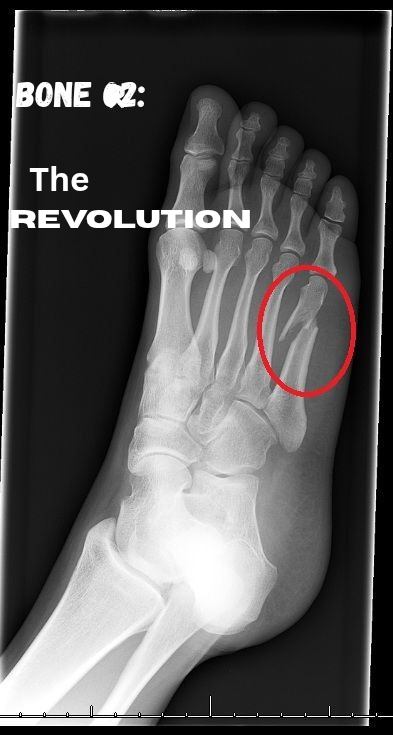

1000853747.png

Caring for patients who undergo orthopaedic surgeries requires a different level of patience and tolerance because they are constantly in so much pain.

During my rotation there, I met a young male roughly in his early twenties who had the most contagious character. Despite the pain from his metal implants, he was always very jovial and tried his best not to transfer aggression to those who were just trying to help him. He was involved in a road traffic accident and sustained so many broken bones and injuries.

Every time we went to carry out a procedure on him that involved his fractured bones, I watched how quickly this free-spirit’s joy was replaced with pain. In such moments, all I could think of was “isn’t there an easier way out”.